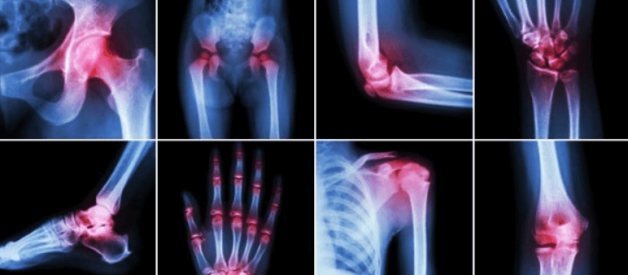

Eklemlerdeki kıkırdağın oluşumunda ve hasarlı kıkırdak dokusunun onarımında büyük öneme sahip bir maddedir.

Kemik, kas ve eklem ağrılarının hissedilmemesini sağlar. Glukozamin kayganlaştıcı etkisi ile eklemler arasında amortisör görevi görerek ağrısız hareket etmemizi sağlar. Eğer bu madde olmasaydı kemiklerin birbirine sürtünmesi sonucu oluşan dayanılmaz ağrılara maruz kalırdık.

Eklem ve kemik ağrısı olanlar için takviye olarak kullanılabilecek harika bir iltihap önleyicidir.

Kıkırdak esnekliğini sağlar. Eklemlerde kemiklerin birbirine sürtmesi sonucu meydana gelen ağrılı şişkinliklerin giderilmesinde anti-enflamatuar etki göstermektedir. Kondroitin üzerinde yapılan çalışmalar eklemlerdeki sertlikleri ve şişlikleri giderdiği, buna bağlı olarak osteoartrit tedavisinde faydalı olabileceği görülmüştür.

Kıkırdağa sağlamlık ve elastikiyet kazandırarak maruz kaldığı basınç ve gerilmeme direnmesini sağlar. Eklem ağrılarını azaltmakla birlikte osteoartrit ilerleyişinin durdurulmasında yardımcıdır.